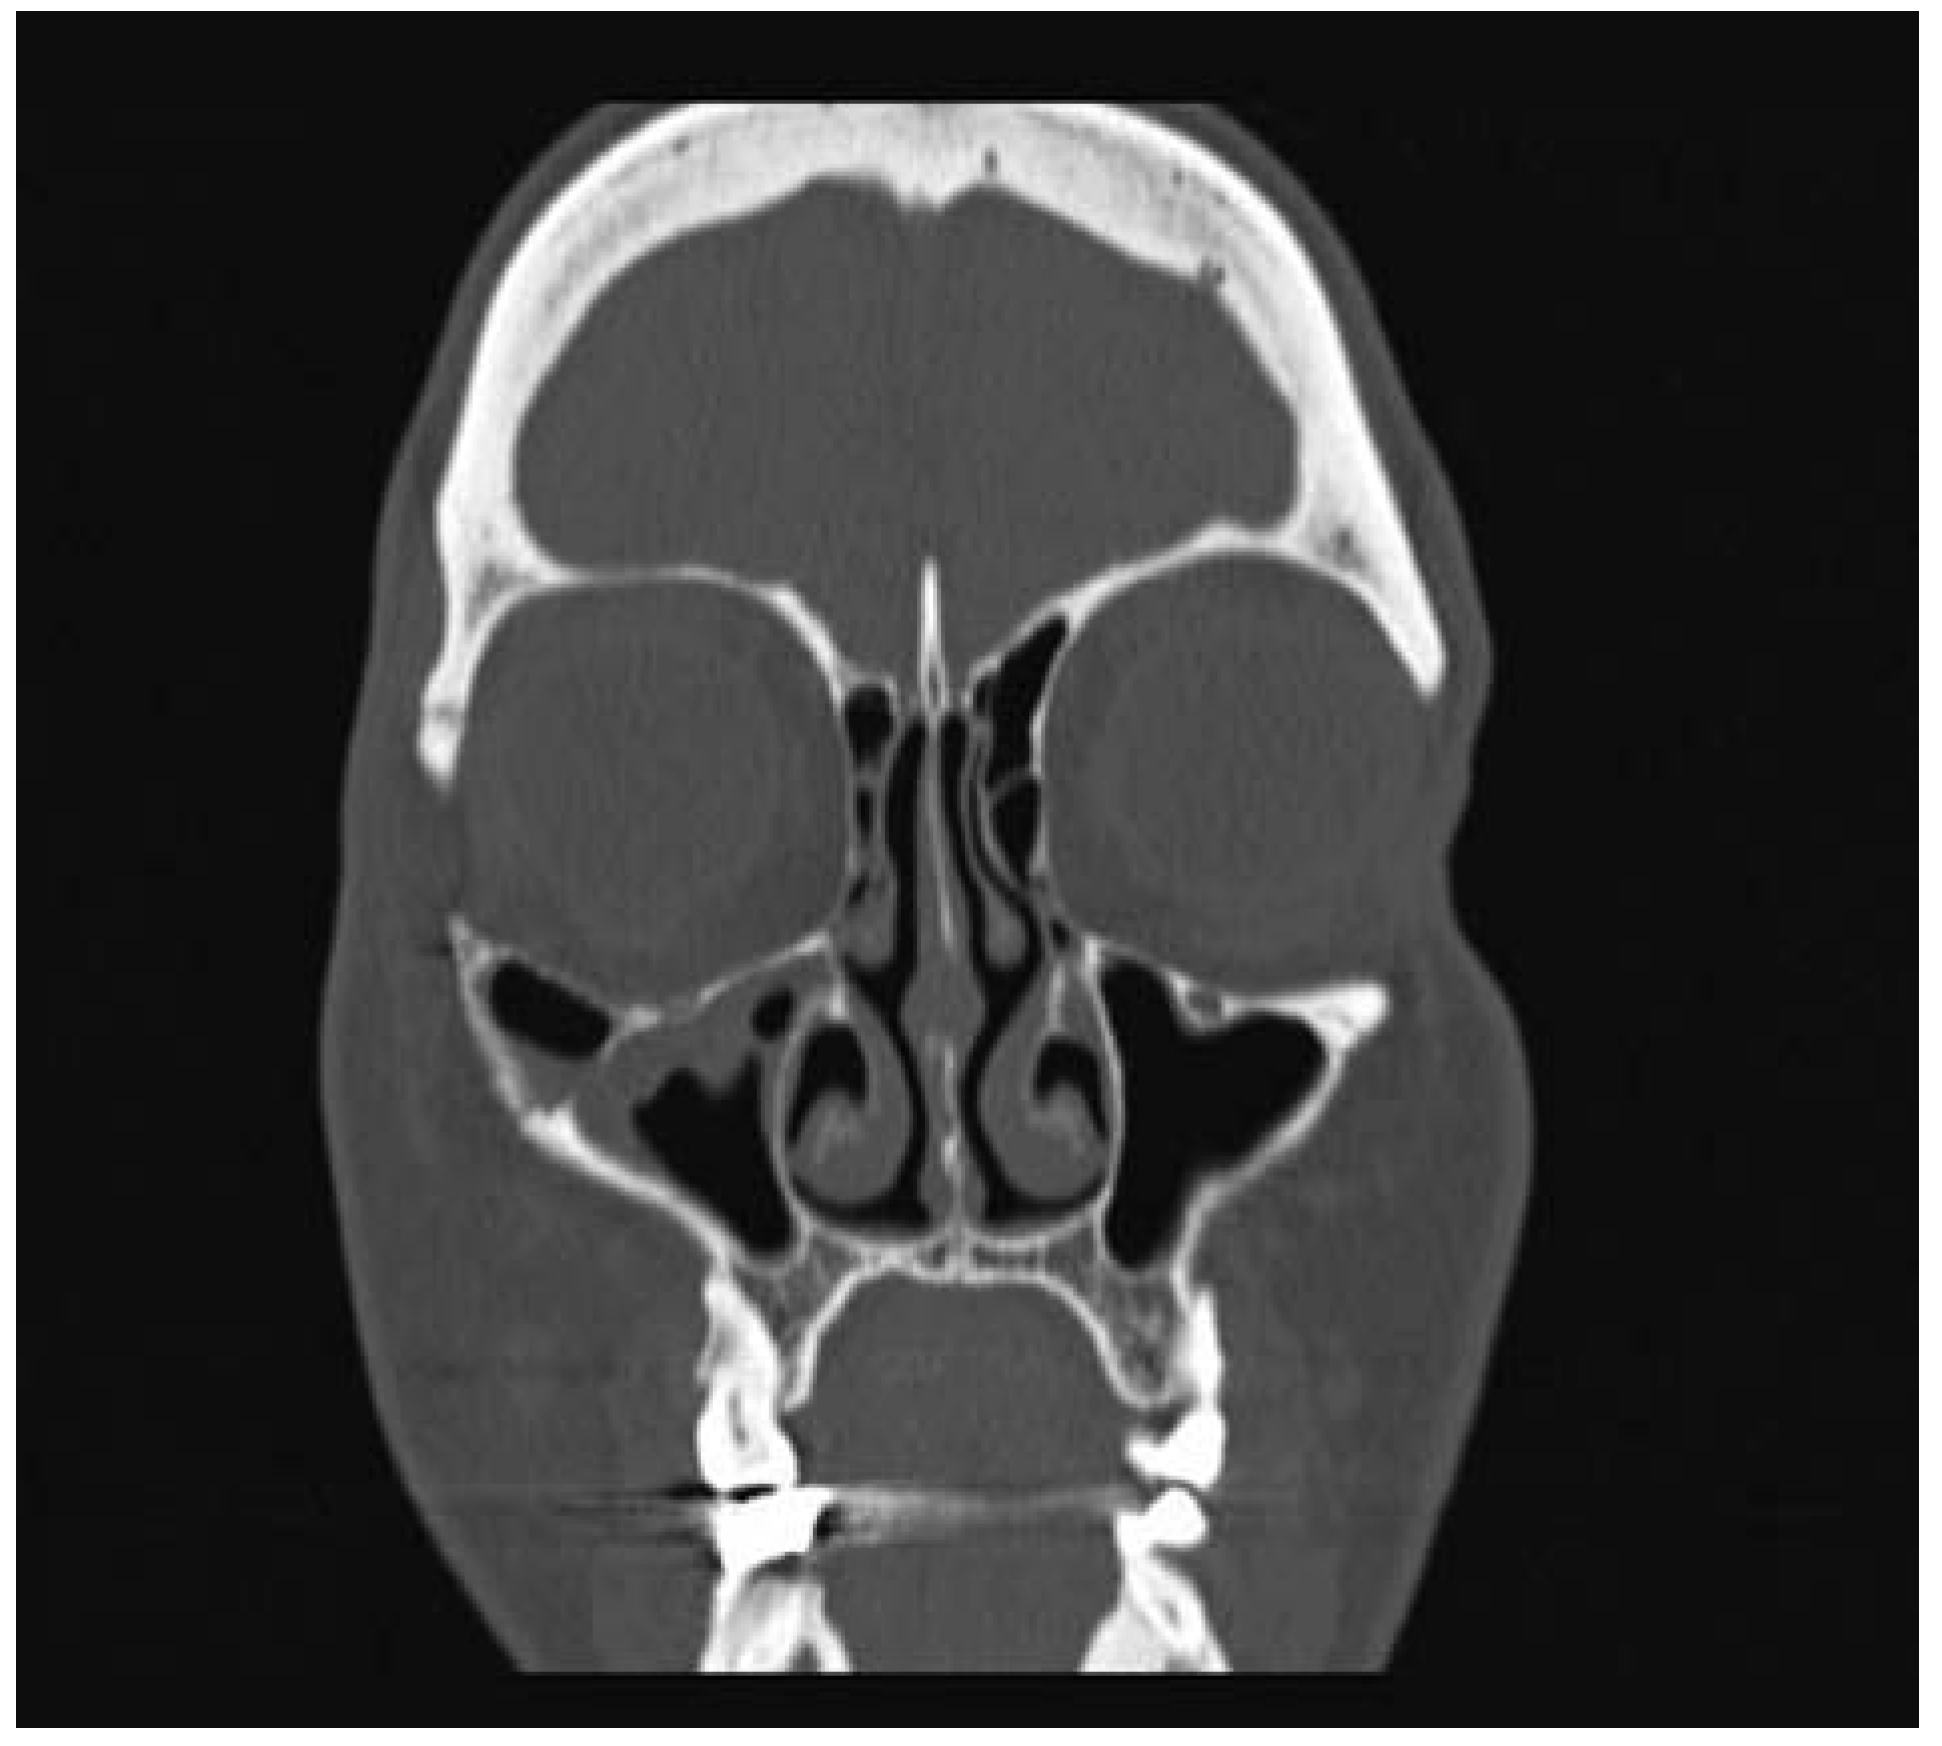

- Moore, S.L.; Chun, J.K.; Mitre, S.A.; Som, P.M. Intraosseous hemangioma of the zygoma: CT and MR findings. AJNR Am J Neuroradiol 2001, 22, 1383–1385. [Google Scholar] [PubMed]

- Razek, A.A. Imaging appearance of bone tumors of the maxillofacial region. World J Radiol 2011, 3, 125–134. [Google Scholar] [PubMed]

- Gonçalves, F.G.; Rojas, J.P.; Hanagandi, P.B.; et al. Case report: Periorbital intraosseous hemangiomas. Indian J Radiol Imaging 2011, 21, 287–290. [Google Scholar]